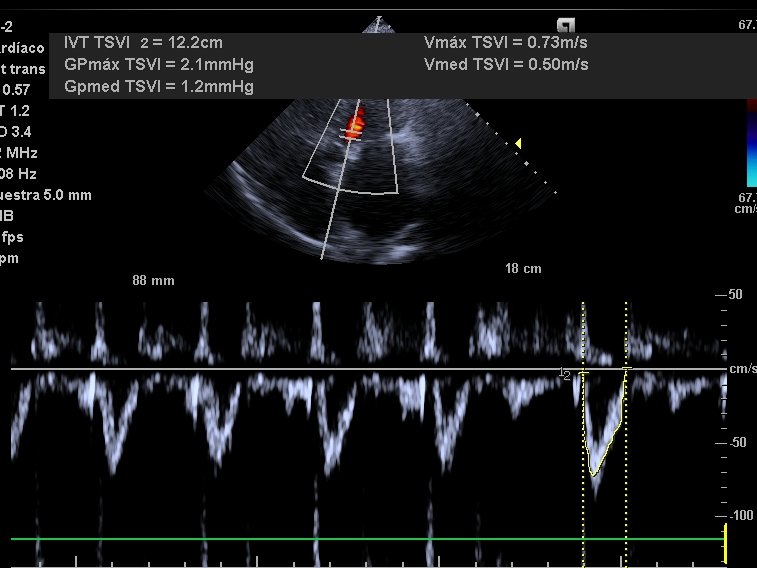

Severe TR in rheumatic🫀 disease with mitral stenosis. Very dilated LA and RA (chronic elevation of pressures), and a small collapsible IVC. Normal Portal Vein (not needed). Average LVOT VTI (atrial fibrillation) = 12

Clear cut case of overdiuresis causing low stroke volume! 2/3